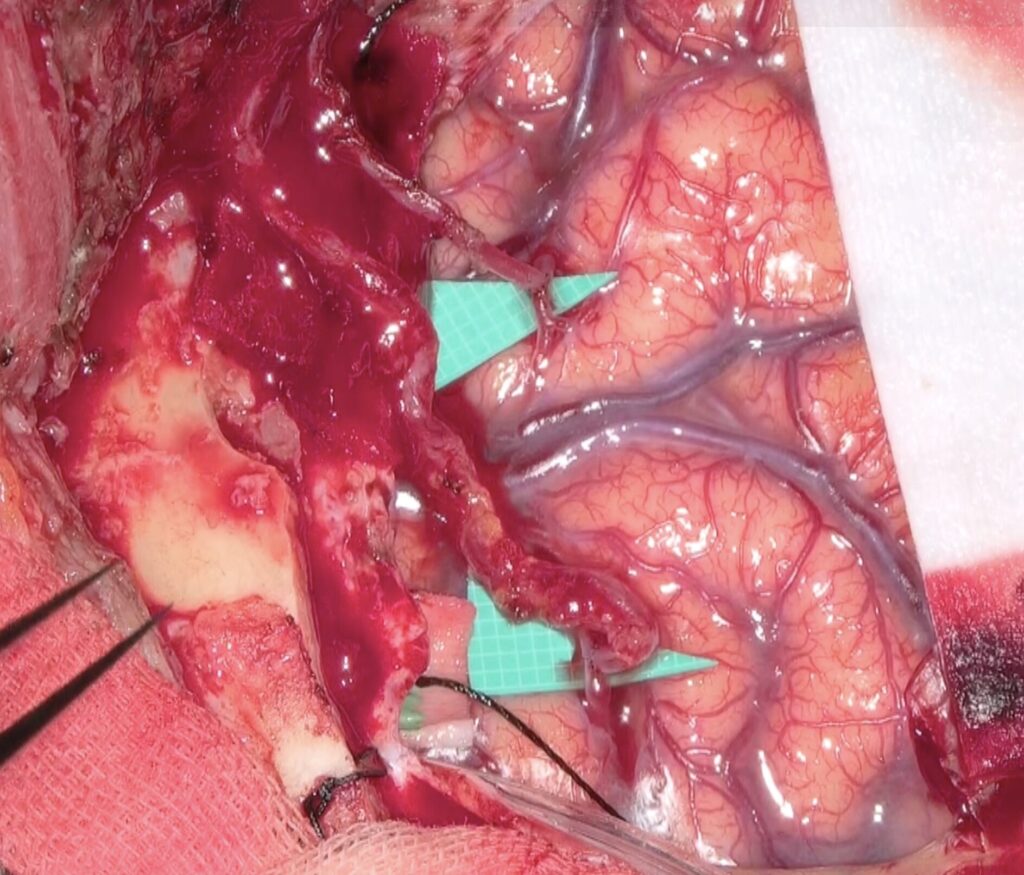

51歳女性の脳梗塞と脳室内出血を続けて起こした左片側もやもや病の患者さんをバイパス手術しました。STAがgaleaから外に出てGaleaの外に枝を出していたため皮弁翻展時にSTA頭頂枝が切れてしまい、端端吻合をしてからバイパスに用いました。2本とも無事開通しました。脳血流が著明に低下していたので術後の過灌流が心配で厳重な術後血圧管理を行いましたが、幸い順調な回復を見せています。

51歳女性の脳梗塞と脳室内出血を続けて起こした左片側もやもや病の患者さんをバイパス手術しました。STAがgaleaから外に出てGaleaの外に枝を出していたため皮弁翻展時にSTA頭頂枝が切れてしまい、端端吻合をしてからバイパスに用いました。2本とも無事開通しました。脳血流が著明に低下していたので術後の過灌流が心配で厳重な術後血圧管理を行いましたが、幸い順調な回復を見せています。